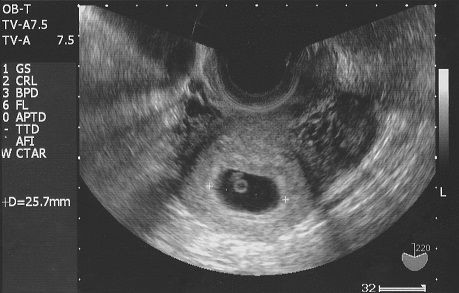

たかこさんの妊娠5週のエコー写真 胎嚢を確認後、不正出血で絶対安静に おなかの中にいる時からそっくり! 今見ても笑っちゃう第1子エコー写真 めまいを覚えたことから妊娠を疑い、その頃は計算上で妊娠3週目程度だったため、そこから2週間待って病院へ。 エコー写真ではまだ胎嚢(中央の小さな縦長の黒い部分)しか確認できません。 2度の流産経験から生理開始日から数えて5週と4日なんです。 一般的には5週後半から6週前半で胎嚢が確認できるってネットに書いてあったんです。 でも、たしか排卵までに今週期は22日くらいかかってたしなぁ・・・ 生理の周期も普段は35日くらいだし・・。今日で5週6日です。 5週4日で初診を受けましたが、 胎嚢が見えませんでした。 出血は無いですが昨日まで腹痛があり子宮外妊娠の可能性は高いでしょうか? 最終生理が12月1日でした。 周期は早くて27日、遅くて34日です

妊娠5週目 的には5週1日で13ミリの胎嚢が確認できてい Posted on 21年8月4日 by yaoguai 的には5週1日で13ミリの胎嚢が確認できていた為、エコーに胎芽が見える頃だと思っておりましたが、胎嚢の中には何も見えませんでした。5w4dと思われる日にエコー撮りました。 171mmとのことで胎芽になっていくであろう物も確認できました。 二週間後の診察が楽しみであり不安ですが、リラックスして待とうと思います。 おなまえ moco ねんれい 38 妊娠週 5w4d 4回目のAIH、5w4dで胎嚢&卵黄嚢 妊娠4週5日目の胎嚢の大きさは、246mmですよね。 この246に30を足すと妊娠3246日となり、妊娠4週446日ということになります。 こう計算してみると、 実際の妊娠週数である4週5日目とそこまで変わりがありませんよね。 ただし、この計算方法の場合、